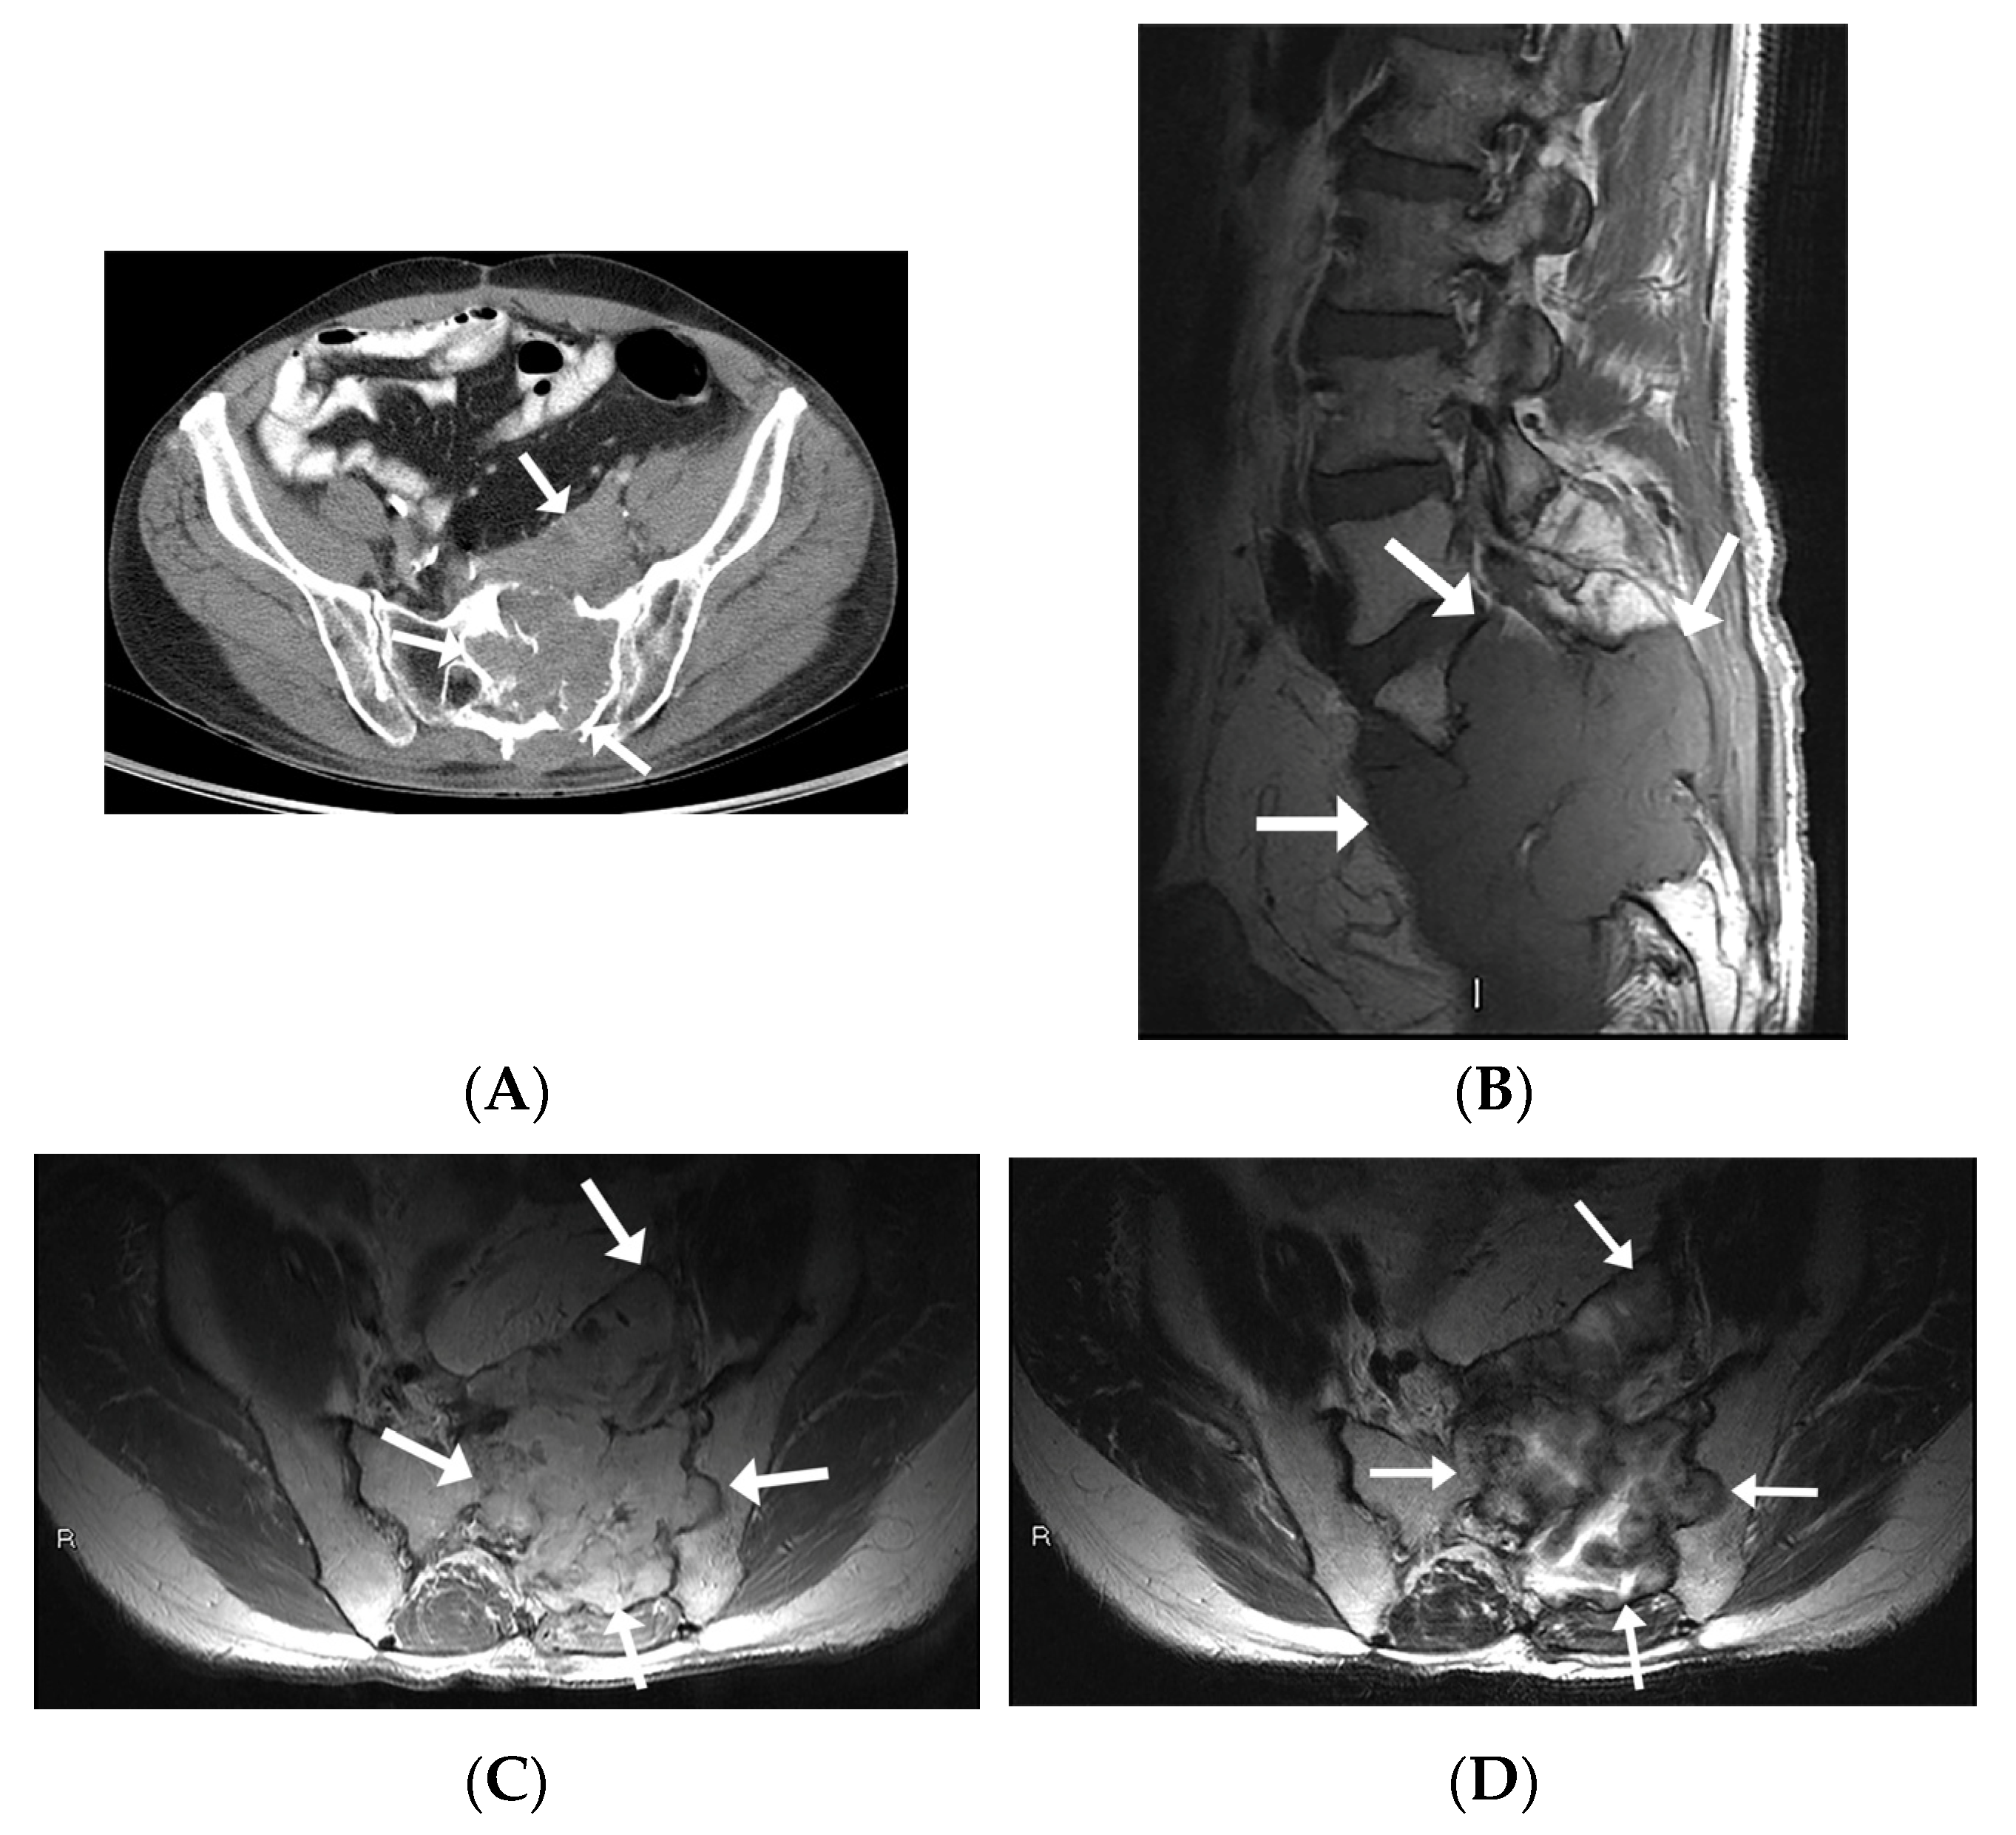

All patients had CT images available. Four patients underwent diagnostic CT studies, while the other two had preprocedural CT images obtained during the CT-guided biopsy. Imaging findings mostly included expansile intraosseous lytic lesions extending into adjacent spaces, including the neuroforamina, epidural space, and central spinal canal (Figure 2C,D). There was one case of a locally aggressive tumor extending anteriorly into the pelvis and posteriorly into the epidural space (Figure 3). The masses were characterized on imaging as heterogeneous, expansile lesions with centrally hypodense areas and peripheral rims of sclerosis.

Figure 3.

MR and CT imaging appearances of intraosseous schwannoma in a 53-year-old man involving the left sacral ala and invading S1-S3 neuroforamina, sacral epidural space, and paraspinous muscles. (A) Axial CT image in soft tissue window shows expansile lytic lesion with invasion into the pelvis anteriorly as well as across the posterior sacral cortex into the paraspinous muscles (arrows). (B) Sagittal T1-WI shows a large multi-lobulated mass involving S1, S2, and S3 vertebral bodies (arrows) with an isointense signal intensity to muscle with invasion and complete effacement of S1 through to S3 neural foramina. (C) Axial-contrast-enhanced T1-WI shows an enhancing mass extending anteriorly into the pelvis, posteriorly into the epidural space, as well as laterally into the left ilium (D) Axial T2WI shows a peripheral intermediate and central hyperintense signal.

3.1.4. Magnetic Resonance Imaging

All IOSs demonstrated consistent signal characteristics on MRI with a low-to-intermediate signal intensity to muscle on T1-weighted images (T1-WI) and heterogenous hyperintense signal intensity on fluid-sensitive sequences. Extra-osseous extension was frequently demonstrated, including invasion into neural foramina with displacement of adjacent nerve roots (Figure 2E,F) and involvement of the epidural space. There was posterior osseous extension from vertebral bodies into the pedicles and spinous processes. There was avid post-contrast enhancement with scattered areas of central non-enhancement.